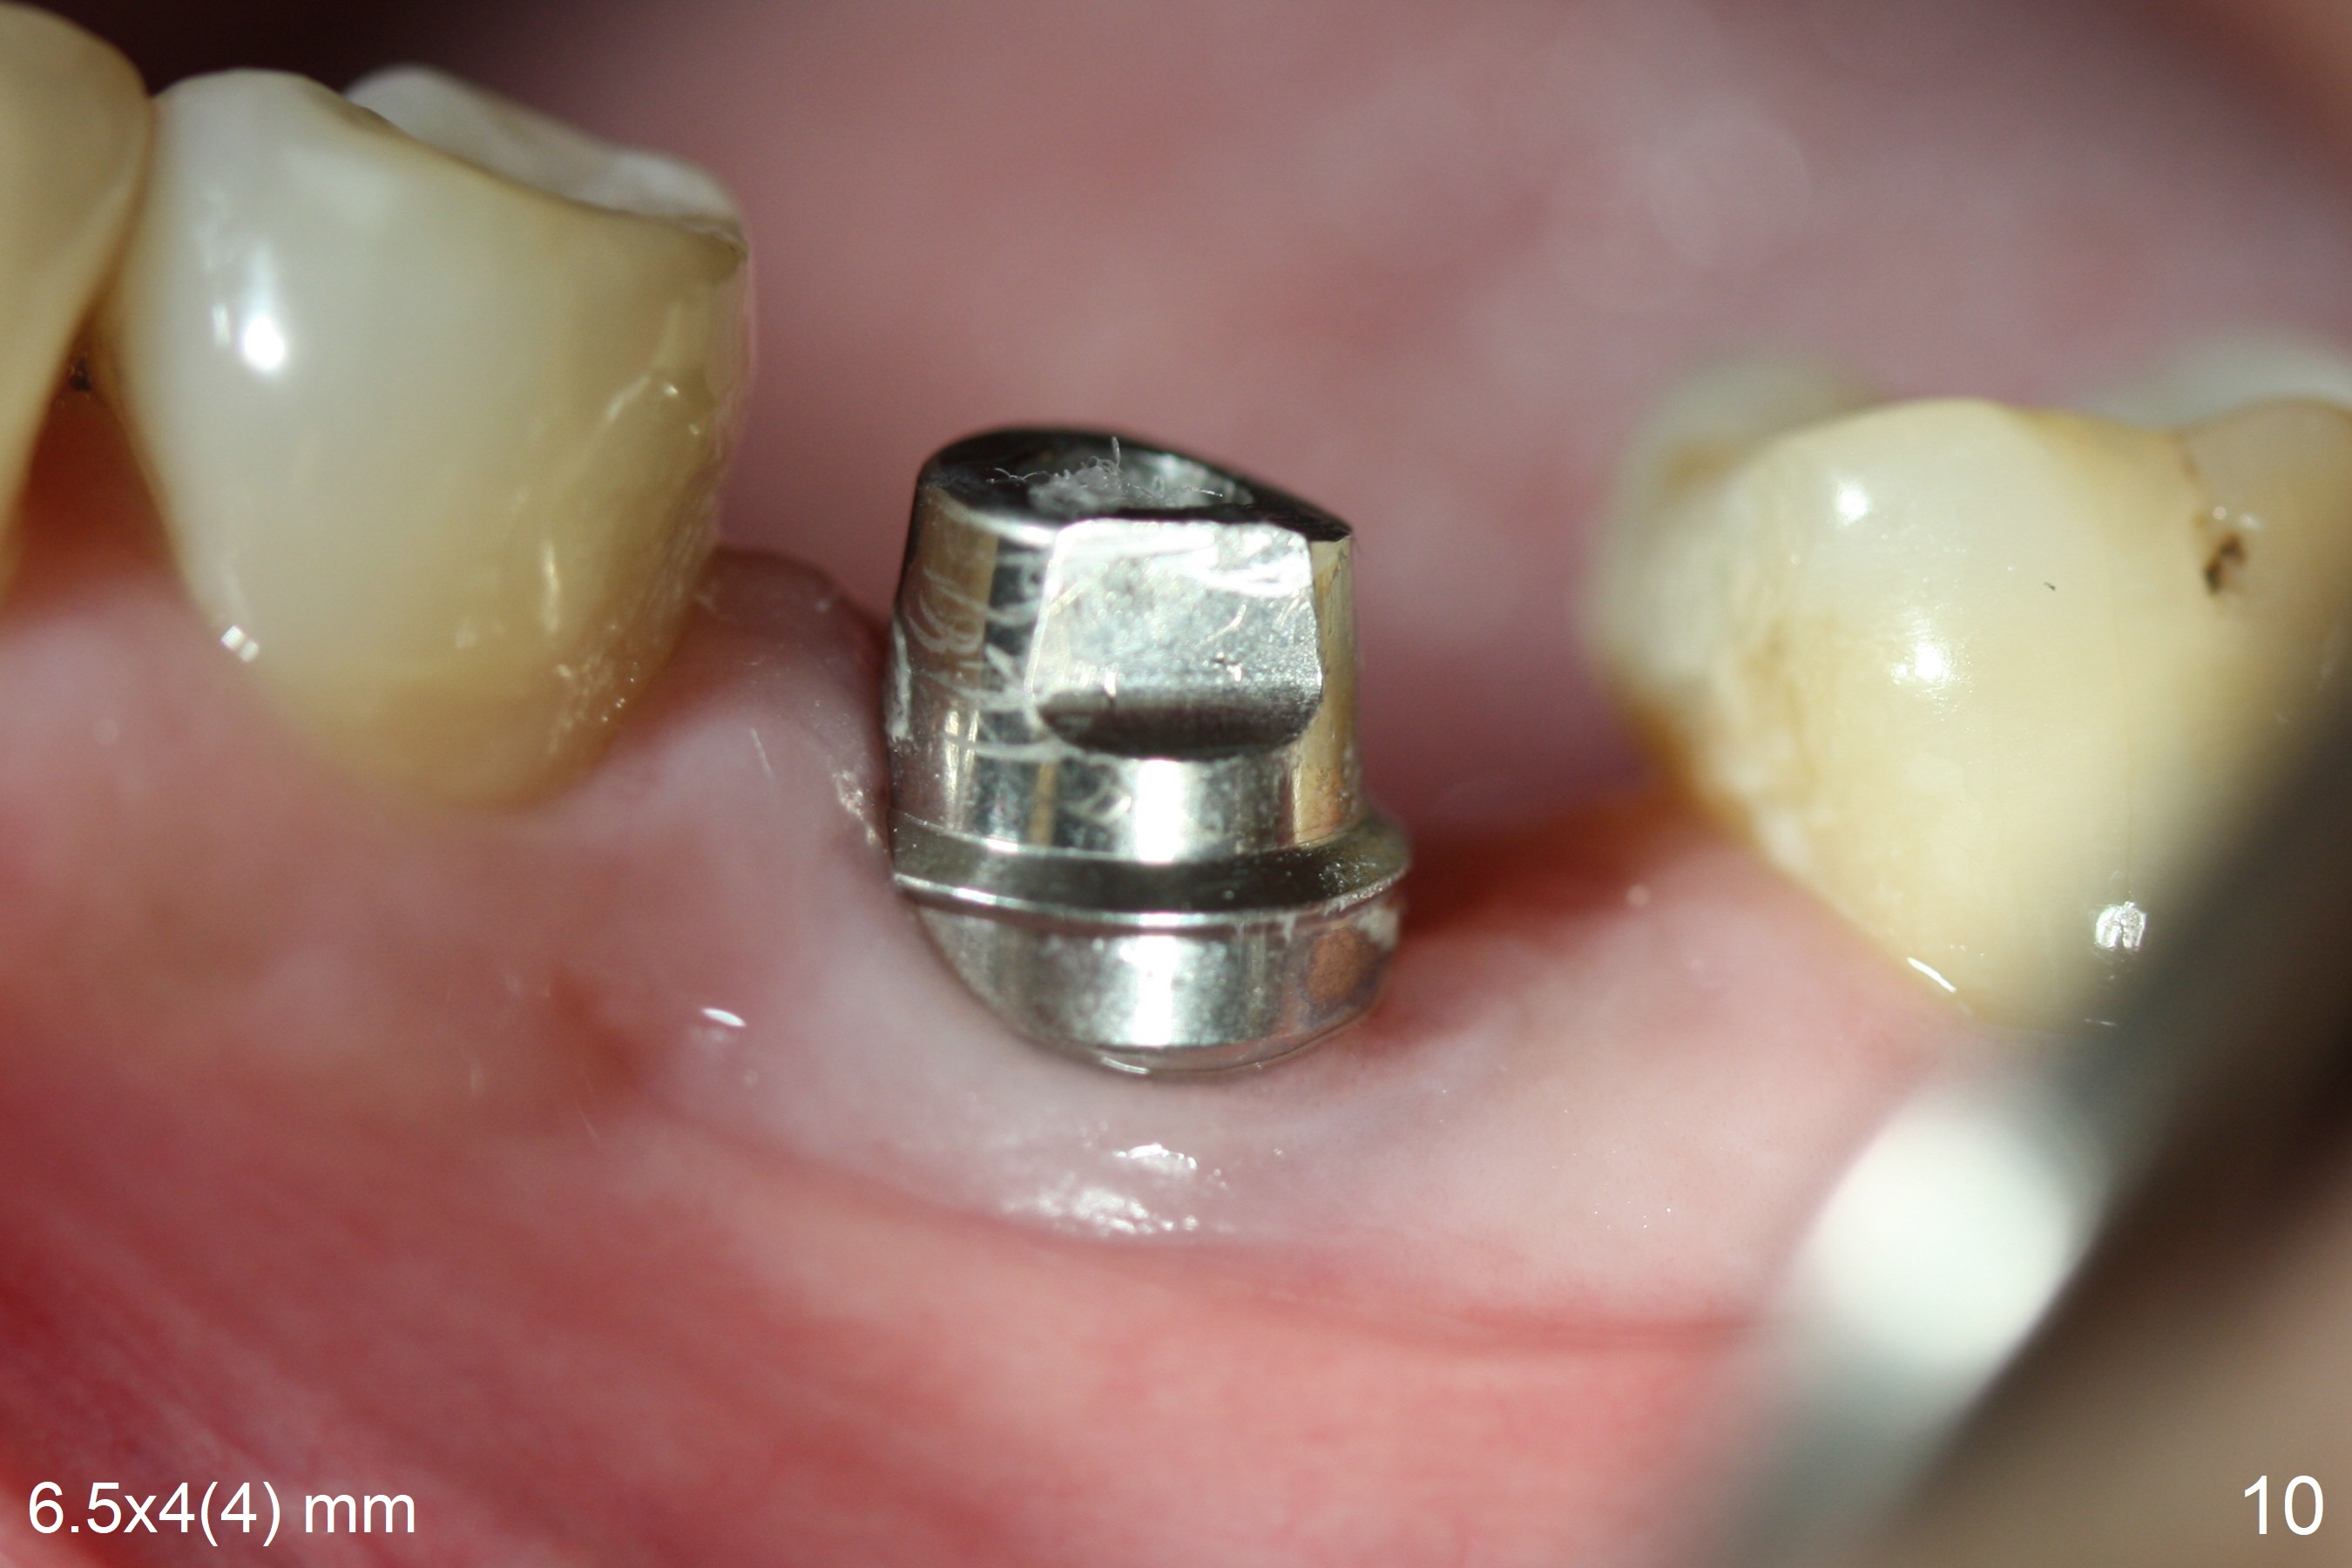

When the patient returns 9 months later, there is severe buccal gingival recession and abscess at #19 (Fig.1 *) with large mesial periradicular radiolucency (Fig.2 *). The septum is thin and the buccal crest is low after extraction (Fig.3 * (mesial root vertical fracture)). Osteotomy is initiated in the mesial socket immediately against the septum (Fig.4.5) with ~ 5 mm in the native bone. Due to severe buccal plate resorption, a shorter implant is placed (Fig.6; 5x15 mm in stead of 18 mm). There is at least 2 mm gap buccally for Vanilla Graft, which is also placed next to the implant and the neighboring root (Fig.7 *). There is clearance from the Inferior Alveolar Canal (Fig.8 red dashed line). Both the mesial and distal sockets heal 5.5 months postop (Fig.9), although the apical portion of the distal socket was not filled with allograft (Fig.7). The implant was placed mesial. The straight abutment (6.5x4(4) mm) (Fig.10) is changed to an angled one (5.5 x15 degrees 3 mm cuff (Fig.11)) before impression. The implant is also placed buccally. Therefore the implant position is far more important than its length. The abutment is retightened 2.5 months post cementation, which is related to mesiobuccal placement of the implant (Fig.12). An ideal trajectory is determined by drawing 2 horizontal lines (at crestal and apical levels: red lines in Fig.13), finding a central point of each line (vertical short line) and joining these 2 central points (Fig.14 pink line). In fact the ideal osteotomy should have been established distal to the septum in this case. Guided surgery may alleviate the issue. The crown is not loose, but the patient feels that the implant tooth cannot sustain mastication. In fact the screw is removed with hand driver (not wrench). The abutment hex is rounded and worn. A new 5.5x4(4) mm abutment is placed (without knowledge of previous use of an angled abutment) with mesial reduction to reduce undercut and buccodistal margin lowered to reduce gingival embrasure. It is that the straight abutment could decrease the chance of screw loosening. Otherwise the implant has to be removed for better trajectory.